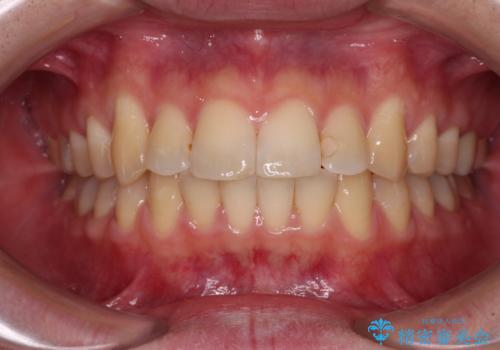

- 奥歯の大きな虫歯により歯が失われてしまい、大きく口を開けると歯がないことが周りの人に見えてしまうことを気にされていた患者様です。

奥歯の欠損部位については、インプラントにより咬めるようにし、その他の虫歯については審美補綴治療を行います。

お仕事で多忙な患者様であったため、治療期間は予定の2倍くらいの期間がかかってしまいました。そのため、治療期間中に仮歯が外れてしまったり、痛みが出てしまったりとご迷惑をかけてしまうことがありました。

すべてのクラウンが装着された後は、痛みやかみ合わせの不具合が解消されたことはもちろん、審美的にも大きく改善され、患者様には大変満足していただけました。